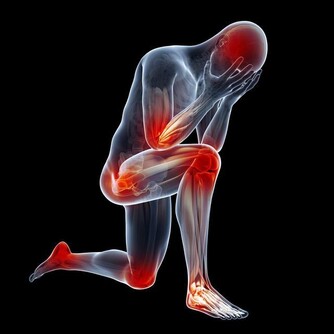

1 、幫你的關節“減負”

你肯定不知道你的關節每天在承受多大的力量,體重每增加1%,關節的承重就會增加4%,我們經常看到很多上了歲數的老年人,走起路來顫顫巍巍,腿都伸不直,可能就是因為在年輕時沒有好好愛護自己的關節,使得關節的使用壽命大大下降了。